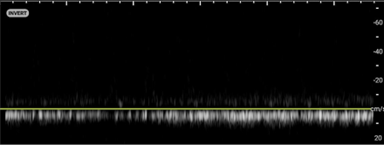

Torsion - Image 1_crop.pngImage 1. Color Doppler of a testicle without blood flow to the body of the testicle concerning for testicular torsion.

In your first image (Image 1), you realize there is no flow with color Doppler. Additionally, you find a torsed cord complex (Image 2), also known as the “corkscrew sign.” You consult Urology who is busy in the operating room with another case. You decide to perform a manual detorsion due to your concern for testicular atrophy and risk of infertility. Using the open book technique, you get relief of pain and return of vertical positioning of the testicle after two rotations. On your repeat testicular POCUS with color Doppler you obtain these images (Images 3 and 4), which demonstrate venous and arterial flow throughout the testicle. The cord is now untwisted and appears linear in orientation.

Torsion - image 3_crop.pngImage 3. Color Doppler demonstrating intratesticular flow toward and away from the probe.